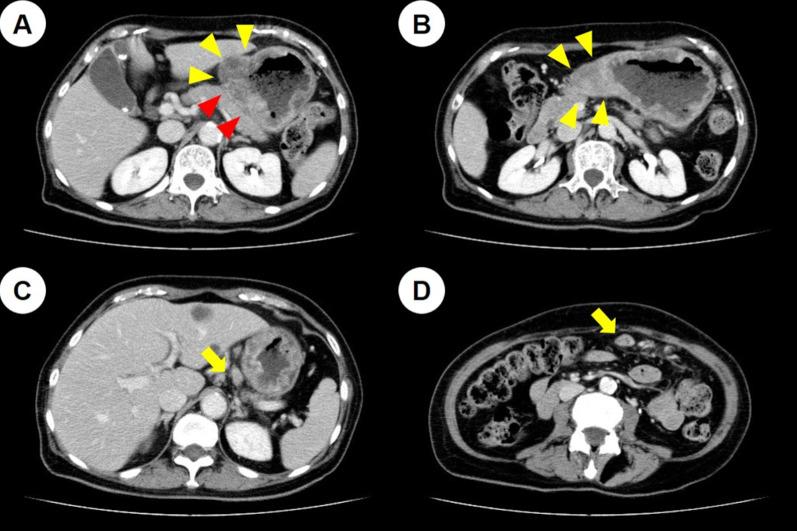

A 73-year-old woman presented with a type 3 tumor in the lower part of the gastric body, which was diagnosed as gastric cancer through biopsy. Staging laparoscopy revealed that the tumor had invaded the pancreas and the posterior lobe of the transverse mesocolon, and disseminated nodules were found near the ligament of Treitz. After 4 courses of S-1 plus cisplatin therapy, laparoscopic gastrojejunal bypass was performed because of difficulty in oral intake. She received S-1 plus oxaliplatin therapy after a gastrojejunal bypass; however, her regional lymph nodes were enlarged. After six courses of paclitaxel plus ramucirumab as second-line chemotherapy, computed tomography (CT) showed exacerbation of peritoneal dissemination; thus, nivolumab was selected as the third-line therapy. The tumor was characterized by MSI-high. At 24 courses, CT and gastroscopy revealed a complete clinical response of the tumor; however, re-growth of the primary tumor was observed at 36 courses. The patient underwent distal gastrectomy with D1 + lymph node dissection, and received S-1 monotherapy as adjuvant therapy for 1 year. No recurrence was noted at 39 months after the surgery.

一名73岁女性,胃体下部有一个3型肿瘤,经活检诊断为胃癌。分期腹腔镜检查显示肿瘤侵犯了胰腺和横结肠系膜后叶,在Treitz韧带附近发现了播散性结节。在接受4个疗程的S-1加顺铂治疗后,由于口服摄入困难,进行了腹腔镜胃空肠吻合术。胃空肠吻合术后,她接受了S-1加奥沙利铂治疗;然而,她的区域淋巴结肿大。在接受六个疗程的紫杉醇加雷莫西尤单抗作为二线化疗后,计算机断层扫描(CT)显示腹膜播散加重;因此,选择纳武单抗作为三线治疗。肿瘤的特征为MSI-H。在第24个疗程时,CT和胃镜检查显示肿瘤有完全的临床反应;然而,在第36个疗程时观察到原发肿瘤复发。患者接受了D1+淋巴结清扫的远端胃切除术,并接受S-1单药辅助治疗1年。术后39个月未发现复发。